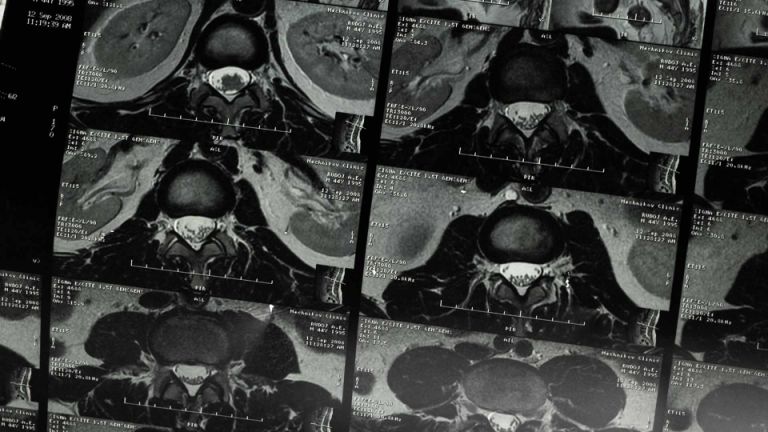

Ketamine is slecht voor je blaas, nieren en urinewegen omdat de drug chemische stoffen bevat die niet in je lichaam thuishoren. In het lichaam wordt de ketamine afgebroken waarbij de chemische afvalstoffen voor pijnlijke ellende zorgen. Via de nieren en urineleiders komen deze giftige stoffen in je blaas terecht waar als het ware een chemische blaasontsteking ontstaat.

Als de blaasontsteking niet geneest en je blaas krimpt zo veel dat hij niet meer kan functioneren, dan word je blaas operatief verwijderd en krijg je een stoma. Op jonge leeftijd rondlopen met een stoma heeft een enorme impact op je geestelijk welzijn en het zorgt dan ook vaak voor psychische problemen.